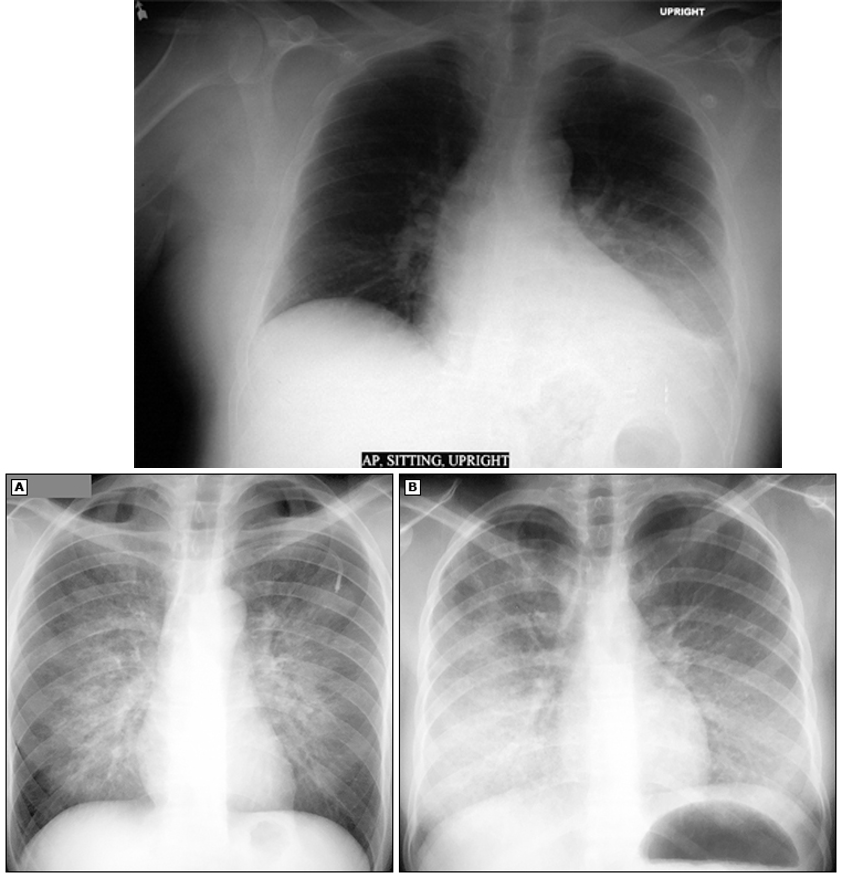

what does this xray show?

aspiration PNA and lung abscess

what does this CXR show?

diffuse grown opacification w/ air bronchograms

what is diagnostic workup for aspiration PNA?

CXR- may show air fluid levels if abscess is present

CT- better at visualization of fluid collections and cavitations

abscess: thick walled solitary cavity surrounded by consolidation and air fluid level

necrotizing PNA: multiple cavitations w/in area of consolidation

empyema: presence of purulent pleural fluid